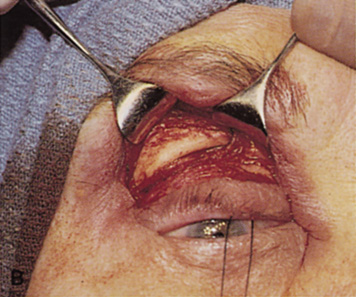

orbital rim can be elevated and osteotomies and removal of the lateral

wall still can be carried out. | Fig. 9. A,B. Coronal and axial CT images of a large intraconal neoplasm. C. Because it was felt to represent a well-encapsulated cavernous hemangioma, this

lesion was a candidate for removal via an eyelid crease orbitotomy

without bone removal. The eyelid crease incision marked. D. Incision made with scalpel. E. Orbicularis muscle is tented up and incised to expose the underlying septum. F. Dissection of a skin-muscle flap deep to orbicularis exposes the orbital

septum and superior orbital bony rim. G. Cutting cautery is used to incise periosteum along the superior and lateral

rims; finger palpation of the bone helps to direct this incision. H. Periorbita is elevated along the mesial surface of the lateral orbital

rim in order to expose the deep orbital tissues. I. The cavernous hemangioma is visualized in the wound. Retraction is provided

by one or more malleable retractors. J. Cryoprobe is affixed to the hemangioma to facilitate manipulation of the

lesion. K. Large cavernous hemangioma after removal through the eyelid crease incision

which was accomplished without bone removal. L. Periorbita is reattached over the lateral rim. M. The eyelid crease incision is closed with a running suture. |